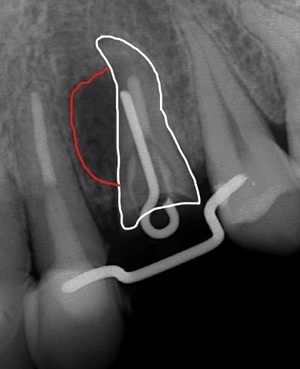

CT撮影 根の脇に大きな病巣を確認。根管治療でのパーフォレーション(穿孔、穴が開く)が原因。

健全な歯根膜を利用して挺出、回転させ、こつの再生を促す。